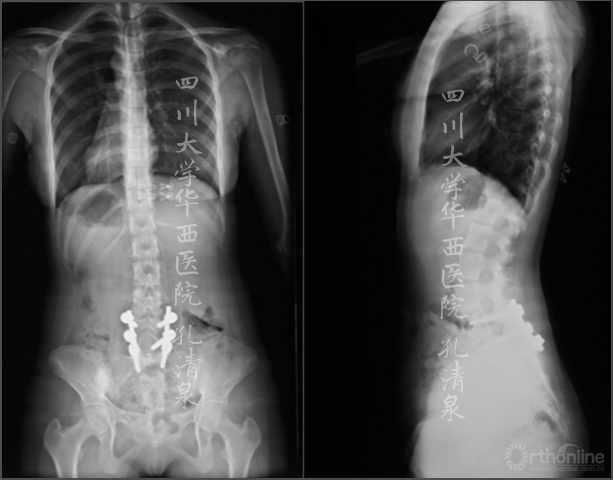

图1 术前X线示:腰5椎IV度滑脱并脊柱侧凸,颈胸弯中立位16°,减轻位0°,胸弯中立位50°,减轻位12°,腰弯33°,减轻位5°,均为非结构性弯。